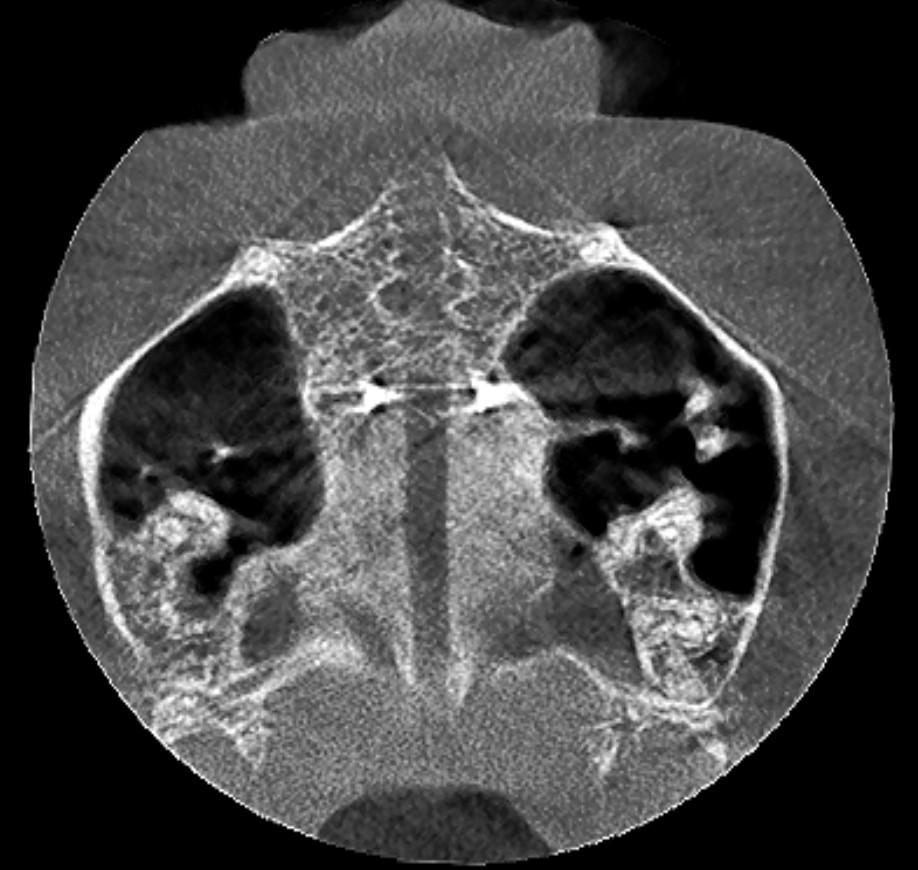

Przekrój CBCT

Przekrój CBCT ukazujący ekspansję na poziomie szwu podniebiennego.